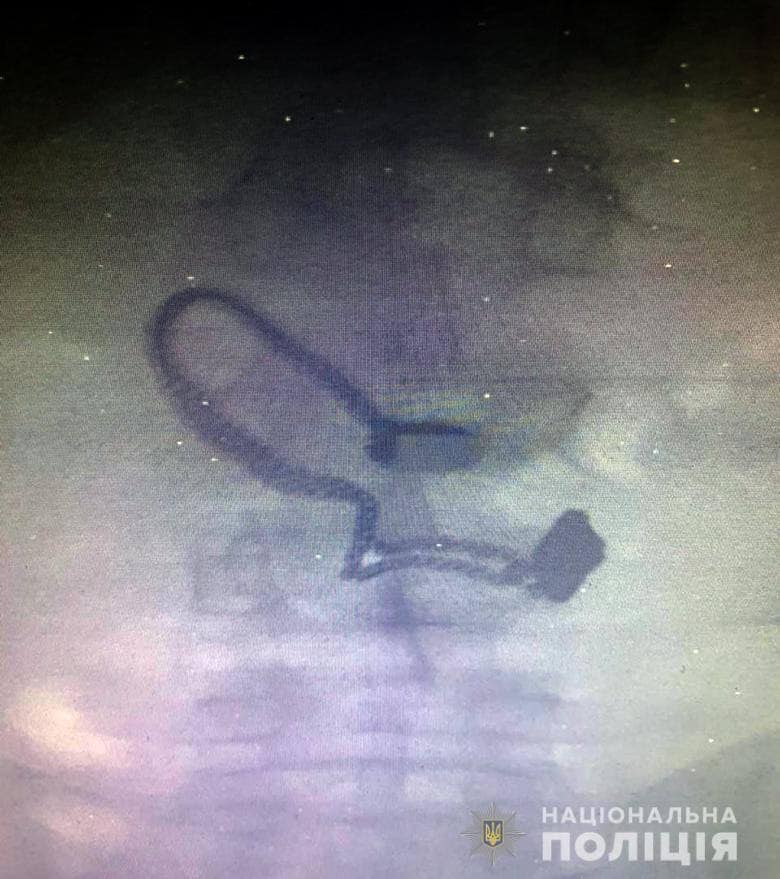

Во время поверхностного осмотра у мужчины нашли кошелек потерпевшей. Впоследствии он признался полицейским, что сорванную цепочку проглотил. Во время медосмотра на рентген-снимке задержанного врачи обнаружили украшение.